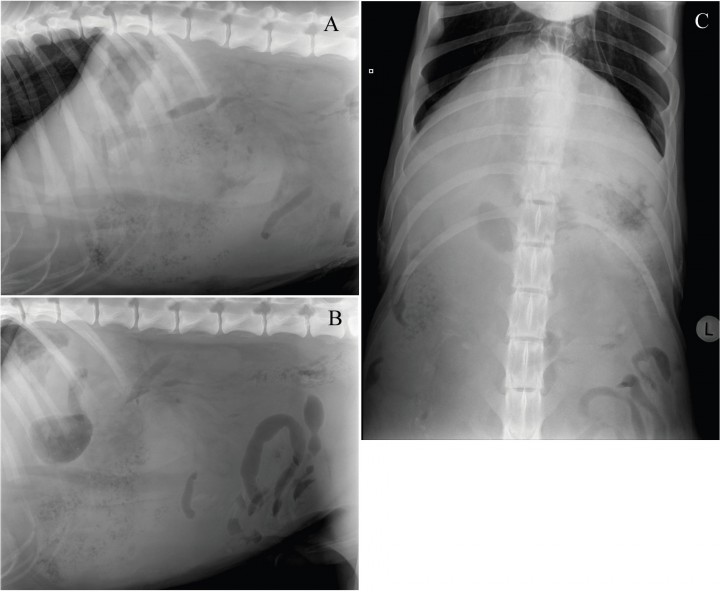

Se observa pérdida de visualización de serosas y una masa localizada en el abdomen craneoventral tanto en el lado derecho como en el izquierdo, con bordes mal definidos, de opacidad tejido blando conteniendo en su interior múltiples focos radiotransparentes irregulares de pequeño tamaño. Las asas de intestino delgado se visualizan desplazadas caudalmente (Fig. 2).

<p>Mismas imágenes que la Fig 1. Se observa pérdida de visualización de serosas y una masa localizada en el abdomen craneoventral (A y B), tanto en el lado derecho como izquierdo (C), con bordes mal definidos, de opacidad tejido blando conteniendo en su interior múltiples focos radiotransparentes irregulares de pequeño tamaño (flechas) desplazando las asas intestinales caudalmente.</p>

Mismas imágenes que la Fig 1. Se observa pérdida de visualización de serosas y una masa localizada en el abdomen craneoventral (A y B), tanto en el lado derecho como izquierdo (C), con bordes mal definidos, de opacidad tejido blando conteniendo en su interior múltiples focos radiotransparentes irregulares de pequeño tamaño (flechas) desplazando las asas intestinales caudalmente.

¿Cuáles son los diagnósticos diferenciales con estos signos radiológicos?

Una masa localizada en el abdomen craneoventral y en ambos lados, lo más probable es que sea una masa esplénica. Los diagnósticos diferenciales incluyen torsión esplénica, esplenitis y neoplasia. Las áreas radiolúcidas observadas podrían deberse, o bien a una torsión esplénica enfisematosa, o a una infección con bacterias formadoras gas. La pérdida de visualización de serosas sería compatible con líquido libre. En base a todos los hallazgos radiográficos se realizó un diagnóstico presuntivo de torsión esplénica enfisematosa o infección con bacterias productoras de gas.

Los signos radiográficos observados en el caso que presentamos aquí coinciden con los descritos en una torsión esplénica, incluyendo el desplazamiento del tracto gastrointestinal y la pérdida de definición de serosas.[ Simeonova G, Simeonov R, Roussenov A: Uncommon cause of acute abdomen in a dog: Torsion of the spleen – Case report and review. Trakia J Sc 2007, 5: 3-4. ] Además, en nuestro caso, el bazo se observó aumentado de tamaño y con múltiples focos de opacidad gas en el interior del parénquima (enfisema esplénico),[ Haller JM, Fabiani MH; What is your diagnosis? Ischemia of the spleen. J Am Vet Med Assoc 2013, 242: 1481-1483. [PubMed] , Jaeger GH, Maher E, Simmons T: What is your diagnosis? Splenic torsion J Am Vet Med Assoc 2006, 229, 501-502. [PubMed] ] también descritos como patrón espumoso[ Patsikas MN, Rallis T, Kladakis SE et al.: Computed tomography diagnosis of isolated splenic torsion in a dog. Vet Radiol & Ultrasound 2001, 42: 235-237. [PubMed] ] o bolsillos de gas. Se piensa que dicha acumulación de gas se debe al crecimiento de bacterias formadoras de gas en el sistema portal, y que éste asciende por la circulación afectando al hígado y al bazo. La causa de la colonización del sistema porto-mesentérico por estas bacterias productoras de gas (Clostridium spp.)[ Gaschen L, Kircher P, Venzin C et al.: Imaging Diagnosis: The abdominal air-vasculogram in a dog with splenic torsion and clostridial infection. Vet Radiol & Ultrasound 2003, 44: 553-555. [PubMed] ] no se conoce con exactitud, pero puede ser debido a alteraciones de la pared intestinal, sepsis intraabdominal y/o isquemia mesentérica.[ Gaschen L, Kircher P, Venzin C et al.: Imaging Diagnosis: The abdominal air-vasculogram in a dog with splenic torsion and clostridial infection. Vet Radiol & Ultrasound 2003, 44: 553-555. [PubMed] ] Sin embargo, otros autores piensan que es de origen no infeccioso y que se debe a la infartación esplénica secundaria, producida por la descomposición de la oxihemoglobina o la liberación de CO2 de los reticulocitos del tejido necrótico sometidos a metabolismo anaerobio, aunque esta última teoría no explicaría el crecimiento positivo a Clostridium spp en algunos cultivos de parénquima esplénico.[ Haller JM, Fabiani MH; What is your diagnosis? Ischemia of the spleen. J Am Vet Med Assoc 2013, 242: 1481-1483. [PubMed] ] En nuestro caso no se realizó ningún cultivo, con lo cual no podemos corroborar ninguna de las teorías descritas previamente.